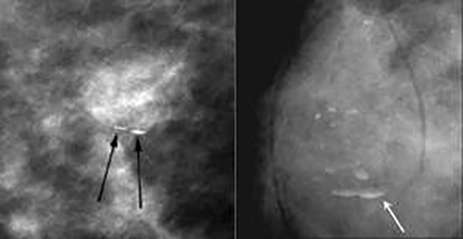

Skin calcifications

Skin calcifications: often polygonal calcifications with radiolucent center

Vascular calcifications

Vascular calcifications: parallel calcifications outlining the vessel wall